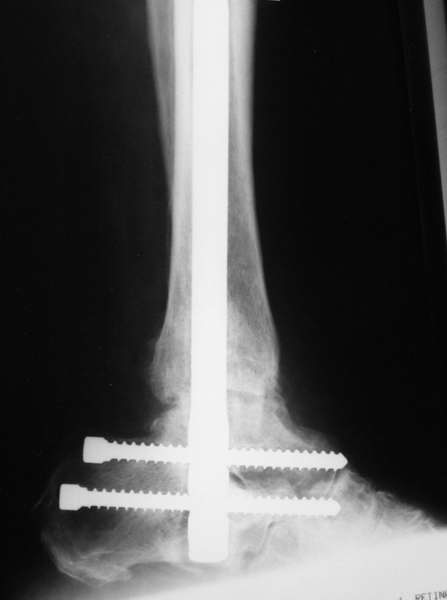

Можно: 65-летняя пациентка, оперирована по поводу несросшегося в гипсе перелома лодыжек с патологической вальгусной установкой стопы и выраженным нарушением опрной функции. Оперирована через 6 месяцев после травмы. Рентгенограммы через 4 месяца после операции.